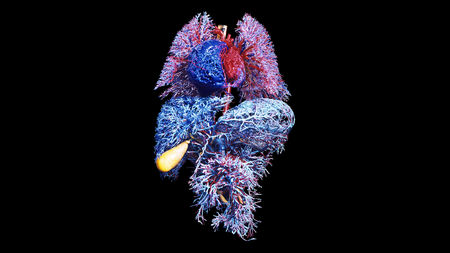

Your Organs Might Be Aging at Different Rates

It turns out that your chronological age really is just a number. What’s more important for knowing disease risk is the biological age of each of your organs